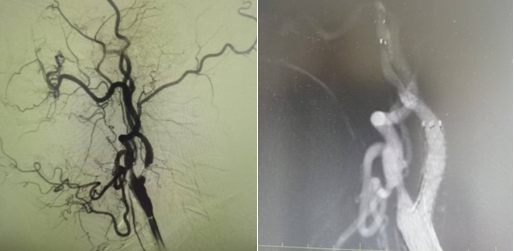

1個(gè)月前姜大爺(化名)反復(fù)出現(xiàn)右側(cè)肢體抽搐癥狀,碾轉(zhuǎn)當(dāng)?shù)囟嗉裔t(yī)院治療,效果不理想,嚴(yán)重影響日常生活,在家人的陪同下來到國文醫(yī)院神經(jīng)介入科。入院后給予行頭MRI彌散+頸部MRA提示:左側(cè)大腦半球分水嶺性腦梗死,左側(cè)頸內(nèi)動(dòng)脈起始處重度狹窄,給予行DSA提示:左側(cè)頸內(nèi)動(dòng)脈起始處重度狹窄至閉塞前改變。

丁金明主任指出:患者反復(fù)抽搐原來是血管狹窄惹得禍,跟患者家屬交代病情后,患者家屬要求血管內(nèi)介入治療,在導(dǎo)管室傾力配合下,順利完成“左側(cè)頸內(nèi)動(dòng)脈起始處重度狹窄支架植入術(shù)”,術(shù)后患者未再出現(xiàn)抽搐癥狀,術(shù)后在醫(yī)護(hù)人員的精心治療和悉心護(hù)理下,患者恢復(fù)良好即將出院。